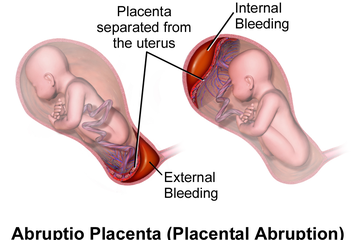

Solusio Plasenta - Gejala, penyebab dan mengobati - Alodokter

Solusio Plasenta - Gejala, penyebab dan mengobati - Alodokter

15 Perbedaan Plasenta Previa dan Solusio Plasenta | HonestDocs

15 Perbedaan Plasenta Previa dan Solusio Plasenta | HonestDocs